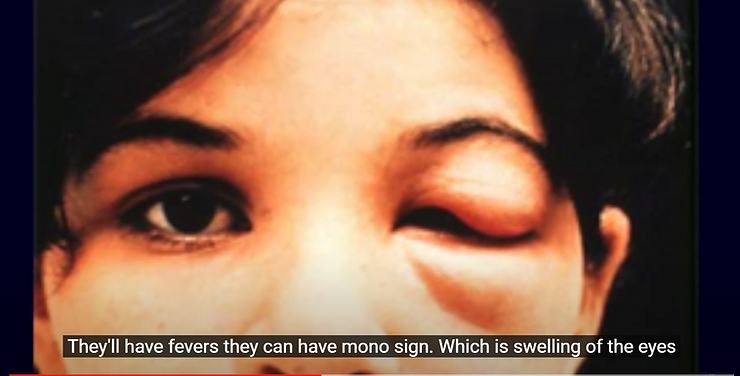

Symptoms of Chagas or Trypanosoma Dis-Ease Include:

1. Fever 2. Headache 3. Body aches 4. Rash 5. Swelling around the eyelids

6. Enlarged heart 7. Heart failure 8. Stroke 9. Life-threatening ventricular arrhythmias 10. Cardiac arrest, and even more life threatening symptomologies listed below . . .